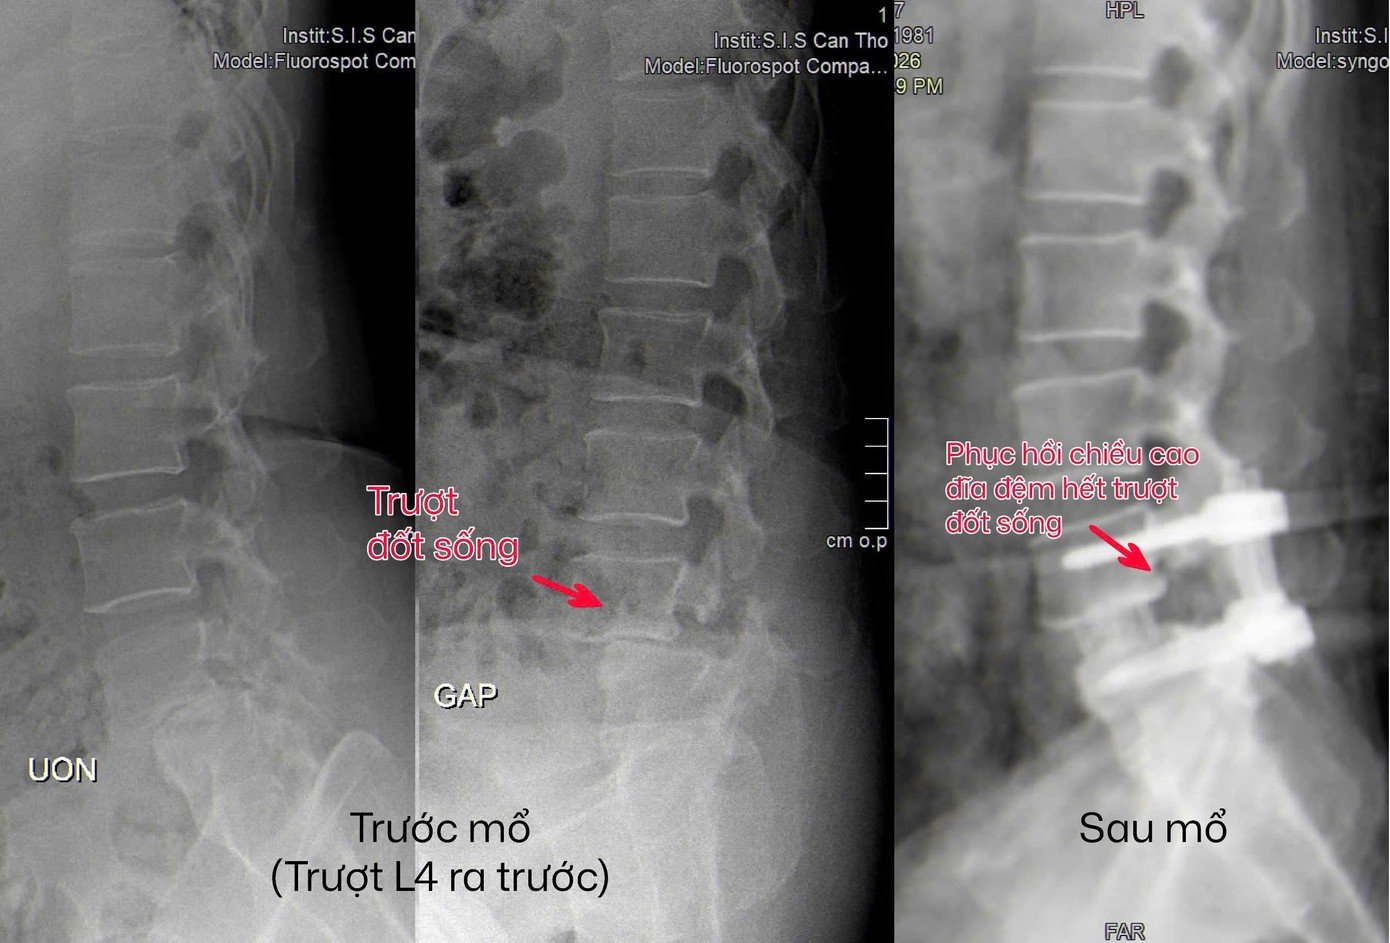

Cuối cùng, chị M. đến Bệnh viện Đa khoa Quốc tế S.I.S Cần Thơ. Qua kiểm tra MRI 3T cột sống thắt lưng, bác sĩ phát hiện chị bị trượt đốt sống thắt lưng mất vững. Đây là tình trạng các đốt sống lệch khỏi vị trí bình thường và không còn ổn định khi vận động.

BS-CKI Nguyễn Quang Hưng, Trưởng đơn vị Ngoại Thần kinh, cho biết không phải mọi trường hợp trượt đốt sống đều cần phẫu thuật. Tuy nhiên, với những ca mất vững và không đáp ứng điều trị bảo tồn, phẫu thuật là cần thiết để tái lập vững chắc cột sống và giải phóng thần kinh bị chèn ép.

Chị M. được thực hiện phẫu thuật nội soi cột sống một cổng, giúp hạn chế tổn thương mô mềm, giảm đau sau mổ và rút ngắn thời gian hồi phục. Ê kíp bác sĩ giải phóng thần kinh, loại bỏ đĩa đệm tổn thương, ghép xương liên thân đốt và cố định cột sống bằng hệ thống vít qua da. Sau phẫu thuật, chị gần như hết đau, đi lại dễ dàng và dần trở lại sinh hoạt bình thường.